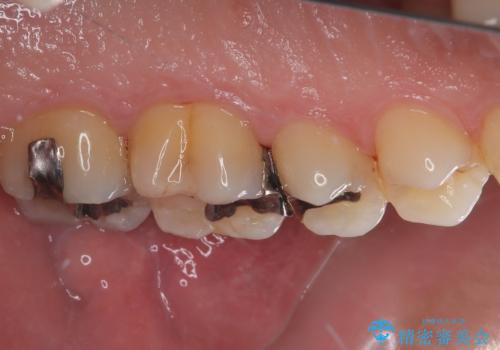

放置した欠損部 奥歯の即時荷重インプラント治療

左下の欠損部を長期間欠損を放置していたことで、咬み合う上の奥歯が動いてしまっている状態でした。

インプラント部は埋入とともに仮歯を装着し、同時に上顎奥歯の部分矯正を開始することとしました。

理想的な咬み合わせに改善した上で、インプラント補綴治療を行うこととしました。

部分矯正を行ったこと治療期間は長くなりましたが、違和感のない咬み合わせを達成することができました。